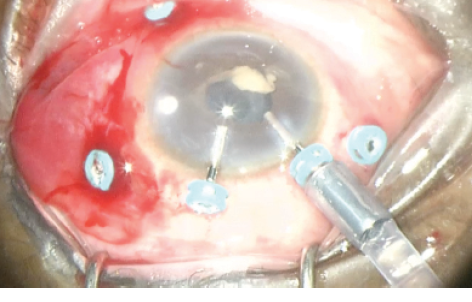

Figure 3. Early vitrectomy for postoperative infectious endophthalmitis. The standard three-port posterior vitrectomy technique is modified with two additional trocar-cannulas at the corneal limbus. This allows anterior infusion placement, which is preferred in eyes in which the media do not allow a posterior infusion line to be verified and checked. The second limbal cannula can be used for the vitrector or forceps for anterior chamber washout and membranectomy of inflammatory membranes. The infusion line can then be moved to the pars plana for posterior vitrectomy, or posterior vitrectomy can be performed with the anterior infusion in place.

Our surgical technique for endophthalmitis recalcitrant to the clinical treatment described above includes a five-trocar setup using three standard pars plana trocar-cannulas and two limbal anterior trocar-cannulas (Figure 3).

The two limbal ports are typically necessary in cases of endophthalmitis that are complicated by significant anterior segment inflammatory reaction and/or media opacity. Anterior infusion is established and verified at the corneal limbus while the second anterior cannula is used for anterior chamber washout and membranectomy of fibrin and inflammatory membranes with the vitreous cutter and/or retinal forceps.

When media clarity is improved and the posterior segment can be better visualized, the infusion line of balanced saline solution can be moved to the pars plana, and a complete posterior vitrectomy can then be performed. In eyes in which pars plana infusion still cannot be visualized, posterior vitrectomy can be performed with the anterior infusion cannula. To see this technique in its entirety, please see the Video.